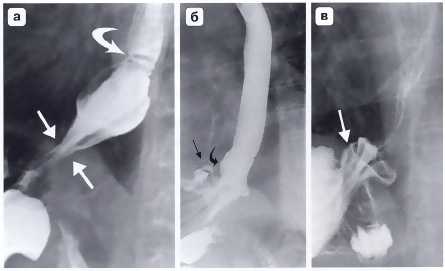

Рис. 4. Осложнения после фундопликации по Ниссену: а — полный разворот манжетки при прорезывании швов; б — соскальзывание кардиального отдела и дна желудка с терминальным отделом пищевода относительно манжетки; в — сформированная вокруг кардиального отдела желудка манжетка; г — втягивание антирефлюксной манжетки в заднее средостение при укорочении пищевода (Черноусов А.Ф. и др.)

Рис. 5. Рентгенограмма. «Соскользнувшая» фундопликационная манжетка: а - соскользнувшая манжетка расположена ниже уровня диафрагмы и сдавливает кардиальный отдел желудка, пищеводно-желудочный переход находится над диафрагмой; б, в - при двойном контрастировании отчетливо видны складки слизистой желудка внутри соскользнувшей манжетки с образованием дивертикулоподобной деформации (подобный дивертикул нередко становится источником желудочно-пищеводного рефлюкса и прогрессирующего рефлюкс-эзофагита) (Черноусов А.Ф. и др.)

Наиболее простым для диагностики и лечения является осложнение «недостаточный» Ниссен. При этом излишне поверхностно наложенные швы на фундопликационной манжетке надрываются, и последняя разворачивается (см. рис. 4, а). С внедрением лапароскопической методики в несколько раз увеличилось число таких присущих ей осложнений, как двухкамерный желудок и перекрученная манжетка. Миграция дна желудка в грудную полость может произойти в раннем послеоперационном периоде, даже в момент выхода больного из наркоза. Происходит это по ряду причин, в частности вследствие необоснованной тракции укороченного пищевода для создания фундопликационной манжетки ниже диафрагмы (рис. 4, г). Неадекватная фиксация фундопликационной манжетки к ножкам диафрагмы предрасполагает к дальнейшему развитию грыжи пищеводного отверстия диафрагмы либо к развитию параэзофагеальной грыжи пищеводного отверстия диафрагмы с перемещением в грудную полость селезеночного изгиба толстой кишки вдоль фундопликационной манжетки (Черноусов А.Ф. и др.).